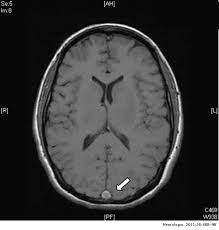

Primer informe de trombosis venosa cerebral después de la vacunación covid con virus inactivado (Sinopharm y Sinovac)